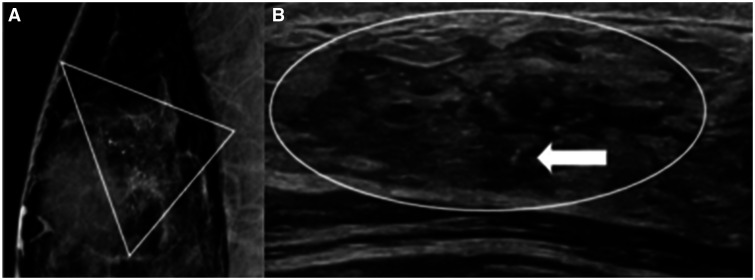

Ductal carcinoma in situ (DCIS) represents a pathologic continuum between a high-risk lesion of the breast and an invasive cancer. Because death from breast cancer is linked to its metastatic spread, the major significance of DCIS is its potential to progress to an invasive cancer and the risk of an occult invasive cancer unrecognized until surgical excision is performed. The standard of care management for DCIS is a minimum of surgical excision, often coupled with adjuvant treatments. For approximately half of the DCIS cases that are at low risk for progression, standard-of-care treatment represents a potential overtreatment and the source of one of the main criticisms against screening. To minimize overtreatment, the tumor biology of any individual's DCIS should be considered in the context of the patient's age, medical comorbidities, and tolerance for risk to tailor personalized treatments. Just as the management of some high-risk lesions of the breast have evolved to include nonsurgical options, it makes sense to personalize the management offered to patients with DCIS. This article reviews the epidemiology, imaging, pathology, ongoing trials, current and possible future treatments of DCIS, comparing and contrasting it with classic high-risk breast lesions and invasive breast cancers.